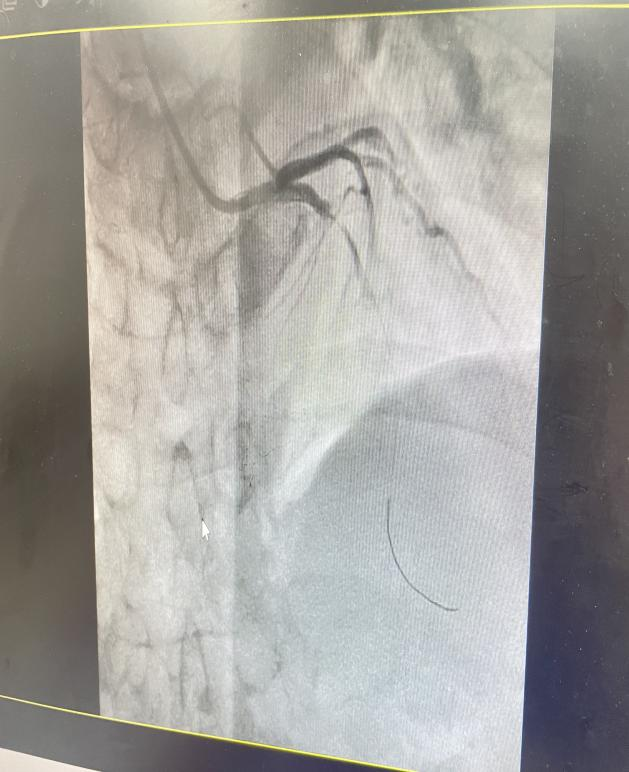

在急诊科初步稳定病情后,心内科团队迅速介入,评估黄叔叔病情并决定立即进行冠脉造影及PCI术以开通闭塞血管。9时48分, 导丝成功穿越患者前降支近段病变处及其远端病变血管进行预扩张时,突发紧急情况!黄叔叔术中出现再灌注恶性心律失常,即室颤,随即失去意识。面对这一危急状况,心内科团队迅速果断实施200焦耳电击除颤,成功使患者室颤转复。然而,在准备支架植入之际,黄叔叔再次陷入室颤危机,心内科团队立即再次进行除颤,同时,护士也迅速建立三路静脉通道,确保抢救药物及时输入。期间,黄叔叔心率波动剧烈,多次在室颤与心动过缓间反复,医护人员通过反复除颤及抢救药物推注等措施,随着前降支支架的成功植入,患者血管畅通,神志逐渐恢复,心率上升,心律终恢复窦性,室颤未再复发。

血管开通前后对比图